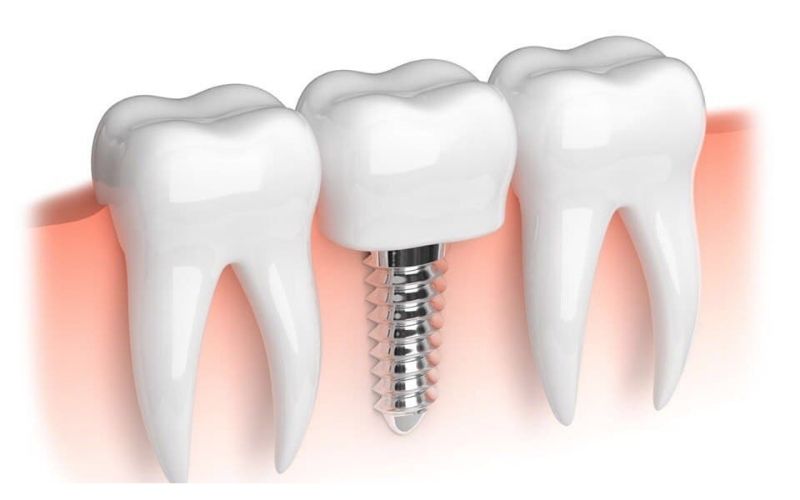

İmplant

İmplant Tedavisi

Titanyum implant kemik içine yerleştirilir, 3–6 ayda kaynaşır, üzerine diş takılarak doğal görünümlü fonksiyon sağlanır.